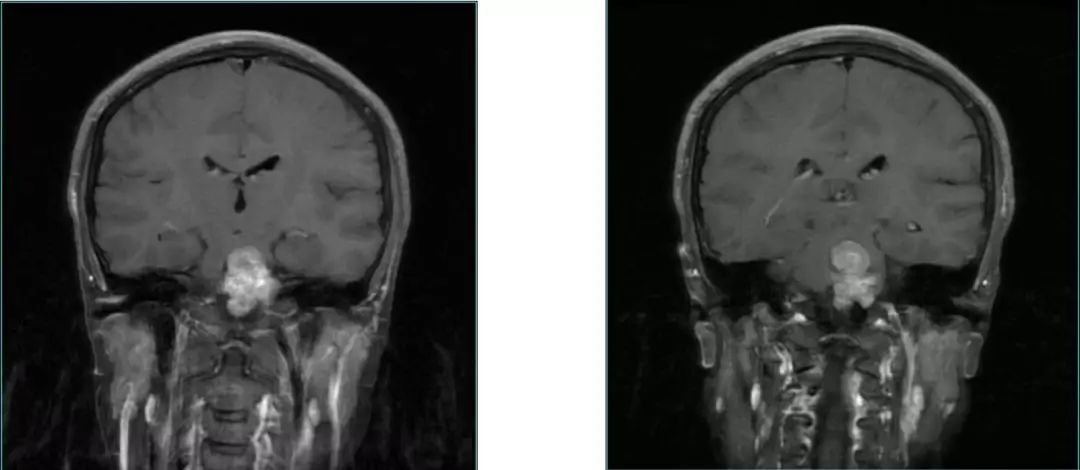

• 22y, Female headache , double Vision for 4 m;

• Examination:GCS 15 scores;abducens nerve palsy

• MRI Images:Reveals occupying lesions in pre-pon cistern, tumor with a upper clivus extension imbedding into brainstem from anterior.  Part of clivus bone is erosion.

Pre-op MRI Contrast